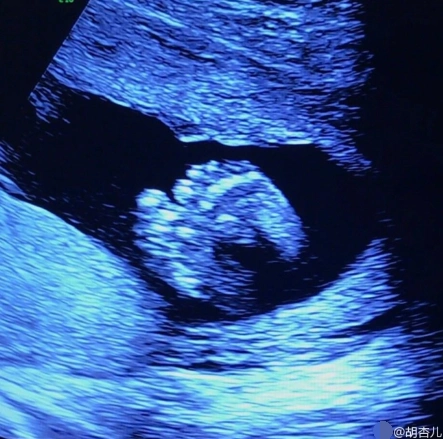

当看到女儿的b超检验结果,她更加不敢相信自己的眼睛——胎儿已经31周

产科b超知多少

孕5个月胎儿大排畸检查:这项检查通过b超检测技术完成,是整个孕育

产检时,若"b超单"上出现这5个字,腹中可能是位小王子

b超检查时,孕妈通过这3组数据,或许能提前知晓胎儿属性的小秘密_宝宝